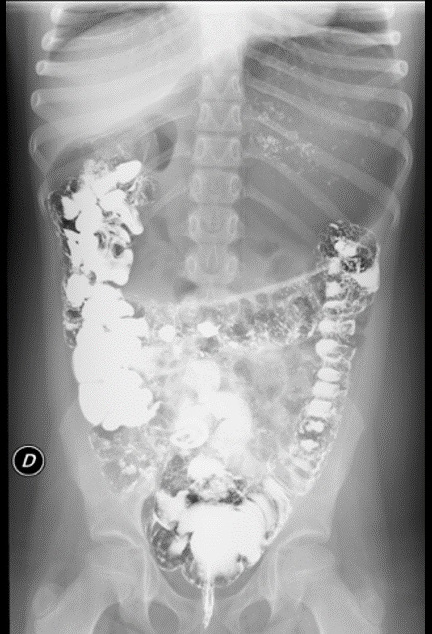

En la exploración física presenta un buen estado de nutrición, con un abdomen marcadamente distendido, timpánico, sin masas ni megalias, no doloroso a la palpación. Se realiza inicialmente radiografía simple de abdomen (Fig. 1), que muestra marcada distensión gástrica y abundante gas en todo el tracto gastrointestinal. Se realiza analítica con hemograma en el que únicamente destaca eosinofilia leve (700 eosinófilos/mm3); bioquímica con perfil hepatorrenal, amilasa y proteína C reactiva normales, hormonas tiroideas y anticuerpos antitransglutaminasa negativos. Estudio de heces con coprocultivo, virus enteropatógenos, toxina de C. difficile y parásitos negativos. Se realiza tránsito baritado (Fig. 2), que muestra marcada distensión gástrica y abundante gas intestinal, con poca motilidad gástrica y paso rápido de contraste a duodeno, sin datos de obstrucción ni vólvulo gástrico. Se completa con una ecografía abdominal sin hallazgos significativos. Tras la realización del tránsito presenta de nuevo importante distensión (Fig. 3), que precisa la recolocación de la sonda nasogástrica. Se produce mejoría clínica tras la descompresión. Se cita en consultas externas para completar el estudio. Se plantea en aquel momento la realización de endoscopia o manometría antroduodenal, para valoración de trastornos de motilidad y la realización de nuevos estudios de imagen como enterorresonancia magnética o incluso laparoscopia exploradora para descartar causa anatómica (vólvulo gástrico intermitente, etc.). El enigma se resuelve a los tres días del alta, tras la expulsión en el contexto de un vómito de un helminto no plano, de 30 cm de longitud, compatible con Ascaris lumbricoides (Fig. 4). Tras la expulsión del nemátodo y la administración de tratamiento con mebendazol oral, presenta buena evolución, manteniéndose asintomática hasta la actualidad.

| Figura 1. Radiografía simple de abdomen que muestra una distensión gástrica llamativa y abundante gas en todo el tracto gastrointestinal |

|---|

![]() |